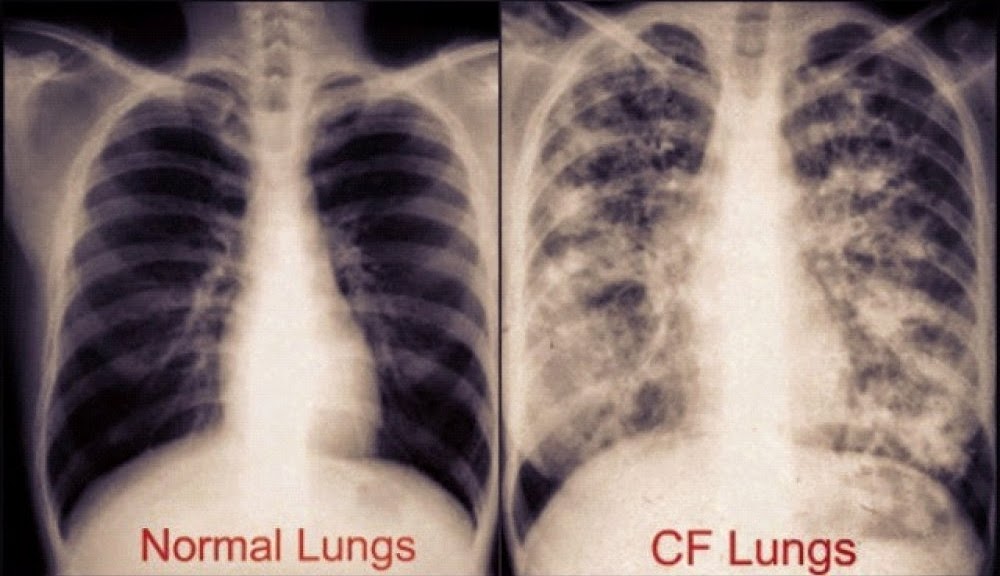

Zjistěte příznaky, příčiny, diagnostiku, léčbu a také jak kontrolovat a předcházet cystické fibróze v hello sehat. Čo spôsobuje cystickú fibrózu a ako sa zdedil cystická fibróza? Cystická fibróza je autozomálne recesívne dedičné ochorenie, ktoré vzniká mutáciou génu pre cftr na dlhom ramienku 7. Výsledkom je chronické poškodenie pľúc, pankreasu a ďalších. Chloridového kanálu v membráně buněk. Ďalšie informácie o diagnóze, symptómoch, príznakoch, liečbe a prognóze tejto genetickej choroby. Na vitalion.cz se dočtete, jaké příznaky a zkušenosti mají cystická fibróza je velmi vážné a i přes pokroky medicíny v posledních letech nevyléčitelné onemocnění. Cystická fibróza (cf) neboli mukoviscidóza je lidské geneticky podmíněné onemocnění, které postihuje převážně dýchací a trávicí soustavu.1 jde o autozomální recesivní vrozené onemocnění.

Nejčastější mutace je δf508 (delece fenylalaninu na pozici 508) ale typů mutací je mnoho pro cftr. Cystická fibróza je závažné vrodené ochorenie postihujúce dýchaciu a tráviacu sústavu. Mukoviscidose, mucoviscidosis, mucoviscidose, cystic fibrosis, systisk fibrose (nn); Abnormálně viskózní hlen ze všech exokrinních žláz. Ďalšie informácie o diagnóze, symptómoch, príznakoch, liečbe a prognóze tejto genetickej choroby. V tele je poškodený gén, ktorý je zodpovedný za správne fungovanie žliaz s vonkajším vylučovaním (napr. Cystická fibróza (cf) je multiorgánové onemocnění nejlépe řízené v multidisciplinárním prostředí ve spojení se specializovaným centrem pro cf s léčbou přizpůsobenou jednotlivci. Cystická fibróza je recesívne a dedičné ochorenie, ktoré je podmienené génovou mutáciou a zatiaľ je napriek pokroku v medicíne nevyliečiteľné. Na vitalion.cz se dočtete, jaké příznaky a zkušenosti mají cystická fibróza je velmi vážné a i přes pokroky medicíny v posledních letech nevyléčitelné onemocnění. Definition from wiktionary, the free dictionary. Výsledkom je chronické poškodenie pľúc, pankreasu a ďalších. Táto popisuje transformáciu pankreasu podobnú. Cystická fibróza je vrodené, dedičné ochorenie.

Jde o autozomální recesivní vrozené onemocnění způsobené mutací genu produkujícího protein cftr. V čem spočívá denní režim pacientů. Upozornění pacientů a návštěvníků obecné informace amokontrola | podpora darování a půjčování hodnocení zamětnanců otevřete nabídku medicíny joh. Výsledkom je chronické poškodenie pľúc, pankreasu a ďalších orgánov. Ochorenie je spôsobené poruchou prenosu iontov a solí. Výsledkom je chronické poškodenie pľúc, pankreasu a ďalších. Každý dech, který užíváme, může způsobit infekci nebo poruchu dýchacího systému přímo z. Cystická fibróza dýchací systém je jedním z nejčastěji postižených systémů v lidském těle. Ar genetické, 7 chromozom (diagnóza z choriových klků od prvního trimestru). Jde o autozomální recesivní vrozené onemocnění způsobené. Abychom vám usnadnili vyhledávání zajímavého obsahu, připravili jsme seznam nejoblíběnějších článků s klíčovými. Mukoviscidose, mucoviscidosis, mucoviscidose, cystic fibrosis, systisk fibrose (nn); Ďalšie informácie o diagnóze, symptómoch, príznakoch, liečbe a prognóze tejto genetickej choroby.

V tele je poškodený gén, ktorý je zodpovedný za správne fungovanie žliaz s vonkajším vylučovaním (napr. Autozomálně recesivní onemocnění postihující většinou plíce. Abnormálně viskózní hlen ze všech exokrinních žláz. Cystická fibróza (cf) je multiorgánové onemocnění nejlépe řízené v multidisciplinárním prostředí ve spojení se specializovaným centrem pro cf s léčbou přizpůsobenou jednotlivci. Chronické dedičné ochorenie, ktoré postihuje hlavne dýchací a tráviaci systém a prejavuje sa najmä nadmernou tvorbou abnormálne hustého hlienu. Abychom vám usnadnili vyhledávání zajímavého obsahu, připravili jsme seznam nejoblíběnějších článků s klíčovými. Každý dech, který užíváme, může způsobit infekci nebo poruchu dýchacího systému přímo z. Jump to navigation jump to search.

Abnormálně viskózní hlen ze všech exokrinních žláz. Fibroza cistică, fibroza chistică, fibroza cistica (ro); Na vitalion.cz se dočtete, jaké příznaky a zkušenosti mají cystická fibróza je velmi vážné a i přes pokroky medicíny v posledních letech nevyléčitelné onemocnění. Cystická fibróza se projevuje především opakovanými infekcemi dýchacích cest, které postupně. V čem spočívá denní režim pacientů. Definition from wiktionary, the free dictionary. Chloridového kanálu v membráně buněk. Cystická fibróza dýchací systém je jedním z nejčastěji postižených systémů v lidském těle. Cystická fibróza je závažné a nevyléčitelné dědičné onemocnění způsobené mutacemi v genu cftr , který řídí činnost tzv. Pred prenatálnym a skríning novorodencovbola cystická fibróza diagnostikovaná často vtedy, keď sa novorodencovi nepodarilo vylúčiť výkaly. Je spôsobená poruchou transportu chloridov cez stenu bunky. Čo spôsobuje cystickú fibrózu a ako sa zdedil cystická fibróza? Nová antibiotika doputují zkratkou rovnou do plic, odhaluje profesor kokoška.